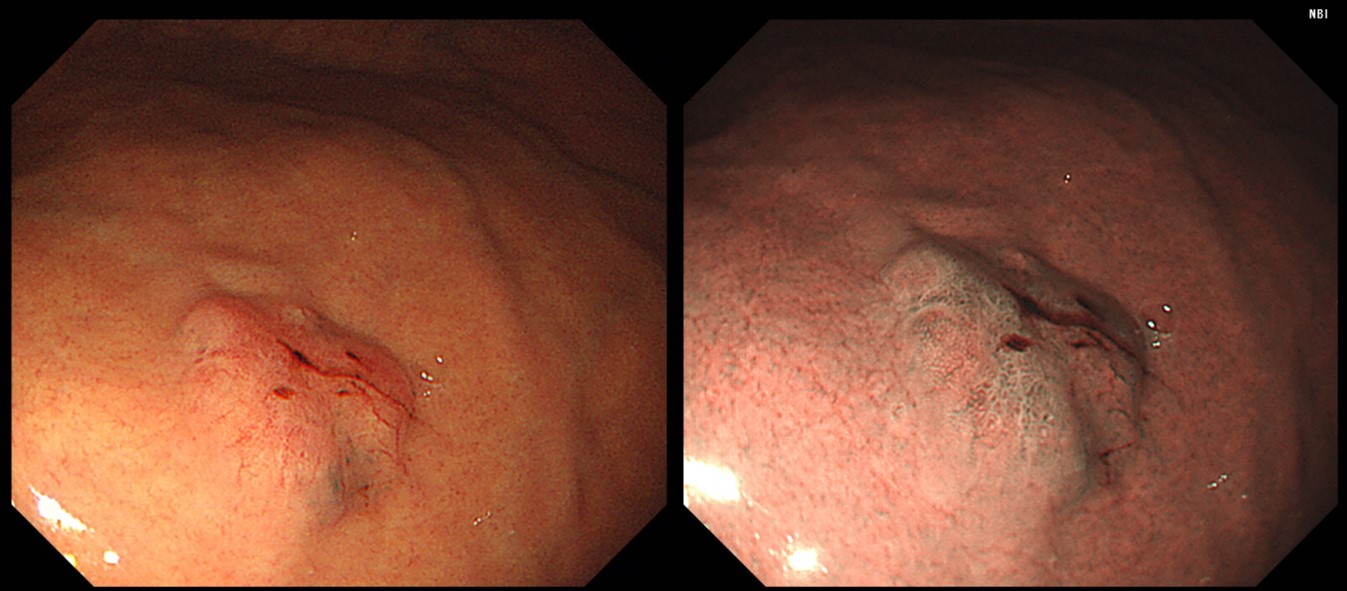

¿¹Á¦ 3 (Âü°í: EndoTODAY Á¶±âÀ§¾Ï ¾ÆÆ²¶ó½º) - 'EndoTODAY À§³»½Ã°æ »ðÀÔ°ú °üÂû' Áõ·Ê 04 (118ÂÊ)